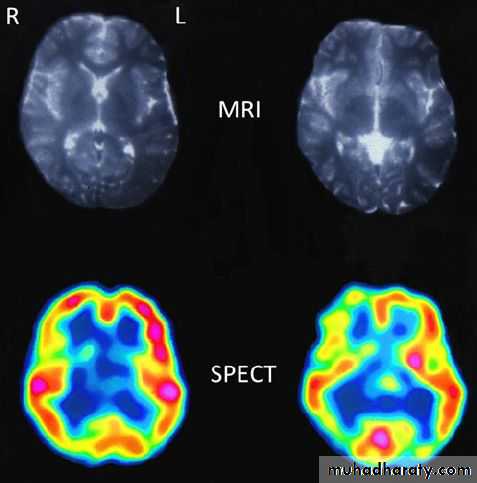

Magnetic resonance imaging: MRI

▪ The hydrogen nucleus is a proton whose electrical charge creates a local electrical field. These protons are aligned by sudden strong magnetic impulses. Protons are then imaged with radiofrequency waves at right angles to their alignment. The protons resonate and spin, then revert to their normal alignment. As they do so, images are made at different phases of relaxation, known as T1, T2, T2 'STIR', diffusion-weighted imaging (DWI) and other sequences. Gadolinium is used as an intravenous contrast medium .Advantages of MRI

▪ High quality soft tissue images .▪ MR distinguishes between brain white and grey matter .

▪ MRI has greater resolution than CT (around 0.5 cm(

Radio-isotope (isotope brain scan ,SPECT,PET)

These techniques image function more than anatomy by tracking the uptake and metabolism of radioisotopes.Disadvatages :

Poor spatial resolution .